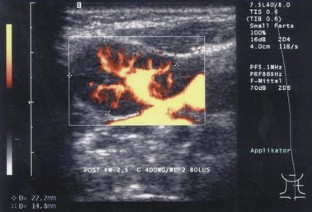

In 55 patients, 40 lymph nodes were correctly categorized as benign and 15 lymph nodes correctly as malignant. The most reliable criteria were shape and vascularization pattern. Intact hilar vessels and branching indicated benign enlargement, destruction of the hilum with vessels running peripherally along the capsule indicated metastatic destruction. Two benign lymph nodes were considered malignant (false positive).

Abb. 3